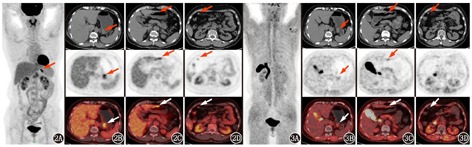

患者女,58岁,因"上腹部疼痛3个月余伴消瘦"就诊。胃镜提示胃多发病变,淋巴瘤可能。病理:考虑为小B细胞性淋巴瘤,倾向黏膜相关淋巴组织(mucosa-associated lymphoid tissue, MALT)结外边缘区淋巴瘤。免疫组织化学分析(图1):细胞角蛋白(cytokeratin, CK;-),CD20(+),CD19(+),CD3(-),细胞增殖核抗原Ki-67(约30%+),B淋巴细胞瘤-6(B-cell lymphoma-6, Bcl-6;-),细胞周期蛋白-D1(Cyclin-D1;-),SOX11(-),CD5(-),CD10(少量+),CD23(部分+),Kappa(+),Lambda(少数+)。碳13呼气试验阴性。为明确淋巴瘤分期行PET/CT(美国GE公司Discovery STE型)显像。18F-FDG(本科室自行制备,放化纯>95%)PET/CT结果(图2A~2C)示胃体上段后壁及胃窦前壁多发局部增厚区,大小分别约1.9 cm×1.2 cm×2.3 cm、4.3 cm×0.8 cm×3.2 cm,黏膜面不规整,FDG摄取不同程度增高,SUVmax分别为5.3和4.0,延迟显像SUVmax为5.1和4.1。胃窦旁大网膜数枚结节影,最大径约1.0 cm,FDG摄取轻度增高,SUVmax为2.1,延迟显像SUVmax为2.0(图2D)。全身其余各部位未见明显肿大淋巴结影,骨髓摄取未见异常。患者知情同意后入组18F-AlF-1,4,7-三氮杂环壬烷-1,4,7-三乙酸(1,4,7-triazacyclononane-1,4,7-triacetrcacid, NOTA)-成纤维细胞激活蛋白抑制剂(fibroblast activation protein inhibitor, FAPI)-46(简称18F-FAPI)(本科室自行制备,放化纯>95%,前体NOTA-FAPI-46由南昌探真生物技术有限公司提供) PET/CT显像临床试验,结果(图3A~3C)示胃壁多发增厚区FAPI摄取轻度增高,SUVmax为2.3,延迟显像SUVmax为2.1。胃窦旁大网膜结节FAPI摄取未见异常(图3D)。